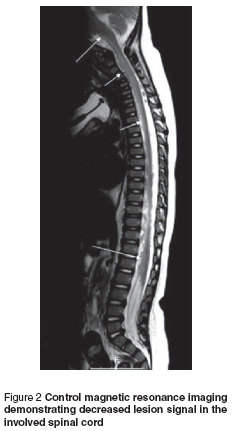

The patient was diagnosed with diffuse myelitis and treated at first with intravenous (IV) immunoglobulin (400 mg/kg/day for 5 days). Response to IV immunoglobulin treatment was delayed for 1 week but because of insufficient remission in his clinical condition, IV pulse methylprednisolone (30 mg/kg/day for 3 days) was started. On day 5 of steroid treatment there was a marked improvement in head control and on day 10 of steroid treatment the patient was able to sit and move his upper and lower limbs independently. Post-treatment magnetic resonance imaging demonstrated decreased lesion signals in the involved spinal cord (Figure 2).